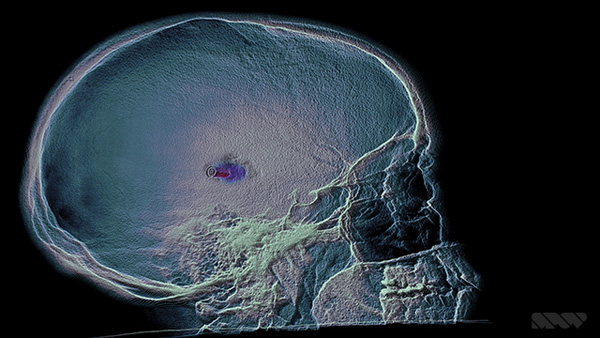

Nevertheless, instead of looking creepy or frightening, the results are strangely beautiful and pull the viewer toward the inner world of brains, bones and blood vessels. This look is no accident. SPOV’s main pipeline is based on Cinema 4D used together with After Effects for compositing – tools SPOV has used for years on nearly all projects and which nearly all of their artists are very familiar with.

Allen said, “For some of the artists here, Cinema 4D plus Creative Cloud software, mainly After Effects, sometimes Photoshop, are the means to create nearly anything. Over time, some have developed skills in 3D software like Maya, or ZBrush as a dedicated sculpting tool. But on ‘Doctor Strange’, although we needed diverse 3D effects, textures and modelling, only Cinema 4D and After Effects were used for everything, including a huge amount of detailed sculpting on some of the assets. We also successfully pushed Cinema’s Proximal Shader to create a smooth, adjustable ghosted effect.

“We could use soft, controllable Boolean operations for the ghosting of hard surfaces. In addition we could render out and animate a black-and-white map precisely determining the cut away areas. Passes were rendered and exported from Cinema 4D, and then layered up in After Effects for compositing.” A nice example of how this looks in the film is in the images above and at the top of this article, showing a portion of the skull cut away to reveal the brain inside.

Looking authentic and attractive in isolation is one thing, but Allen is especially pleased with the way the images look in the movie – not just on darkened sets where they glow against a black background but also in fully lit scenes where they integrate completely into the everyday world of the hospital. “Cinema 4D’s tools don’t get in the way of the creative process," he reflected. "It helps us quickly identify the most efficient route to achieve the result we’re seeking – from revolutionary flying vehicles or fantastic game characters, to something as real as an X-ray or MRI scan – and to cut down on iteration time.” www.spov.tv